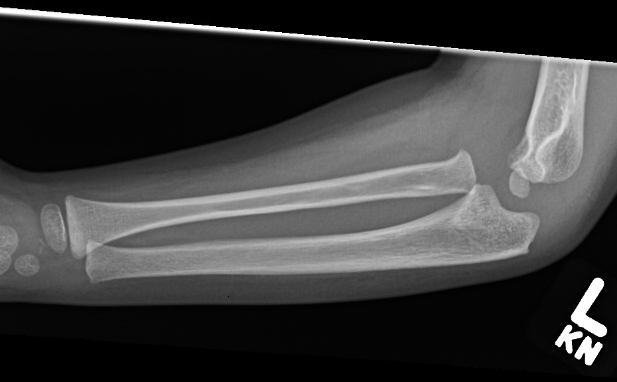

Case 1. Missed Monteggia, injury 6 months ago